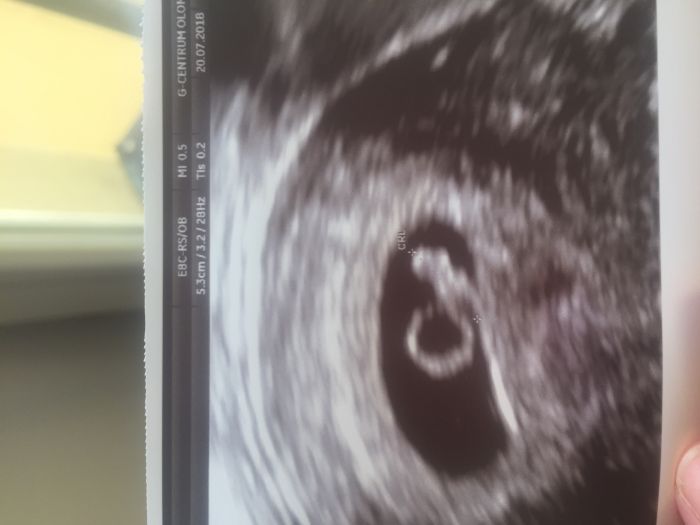

Ahojky holky, byla jsem v patek. Moc moudra nejsem, jsem objednana na ultrazvuk 10.8., ale bobek tam dobre plaval ?